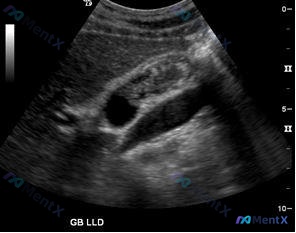

病例资料整理 患者信息:43 岁,女性 主诉:早餐后开始出现腹部不适 现病史: - 报告以前也经历过类似但较轻微的餐后疼痛 - 疼痛性质:痉挛性、反复发作,呈带状分布在胃部区域 - 生命体征稳定 体格检查: - RUQ(右上腹)压痛 - 无反跳痛或警戒感 影像学检查: 1. 图 A(RUQ 超声):...